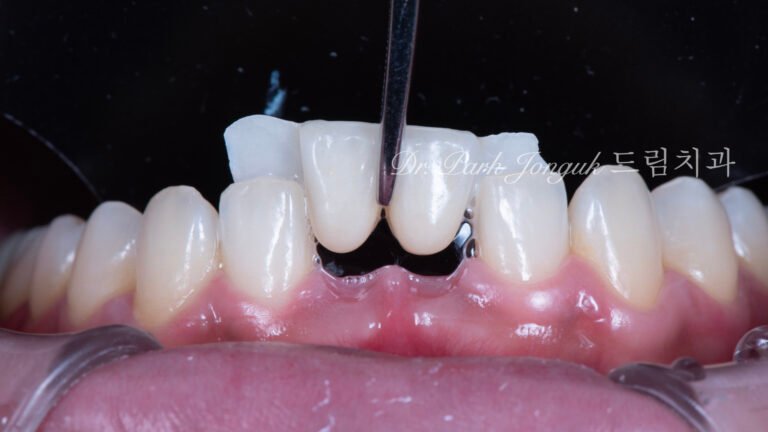

라미네이트 재시술 레이저 제거

치아 손상 없이 라미네이트 재시술을 가능하게 하는 핵심 기술 라미네이트 재시술에서 가장 중요한 단계는새로운 라미네이트를 “어떻게 만드느냐”가 아니라,기존 라미네이트를 어떻게...